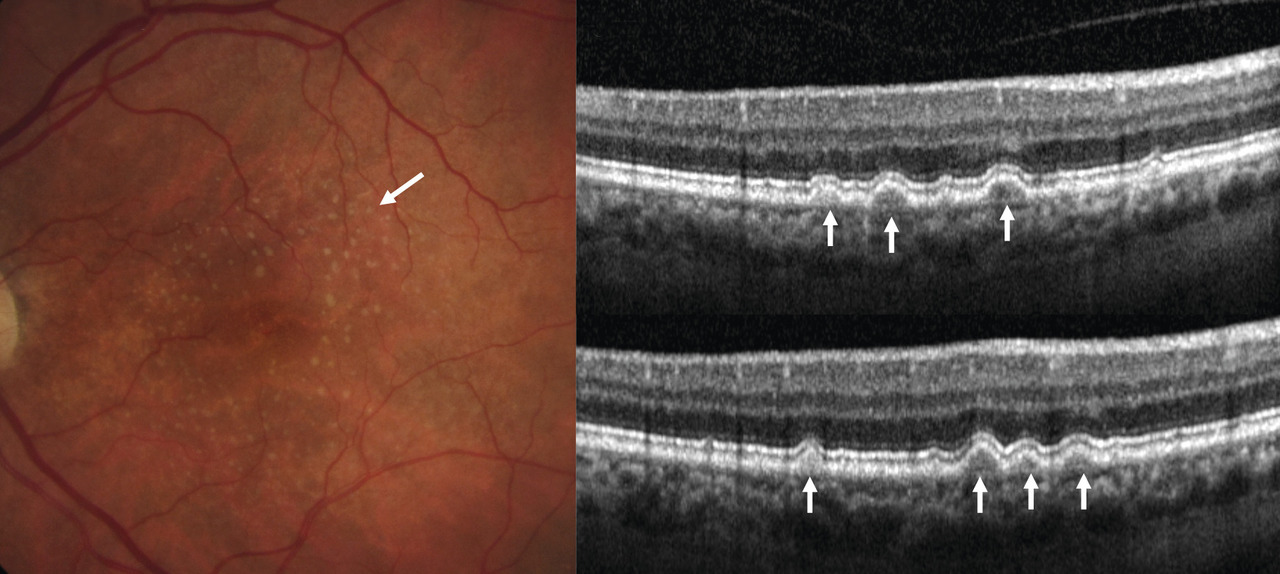

Certains témoignent de la maculopathie liée à l’âge (fig. 3 ) :

– drusen : dépôts jaunâtres sous l’épithélium pigmentaires, de taille variable, parfois coalescents ;

– migrations pigmentaires : taches brunes, ponctiformes, de contour irrégulier. Dues à la mort des cellules de l’épithélium pigmentaire, elles précèdent le plus souvent une DMLA atrophique.

Dans la DMLA précoce, on visualise les drusen (lésions hyperréflectives sous l’épithélium pigmentaire). La rétine en regard est d’épaisseur normale, il n’y a pas de signes exsudatifs (DSR, œdème maculaire) [fig. 3 ].